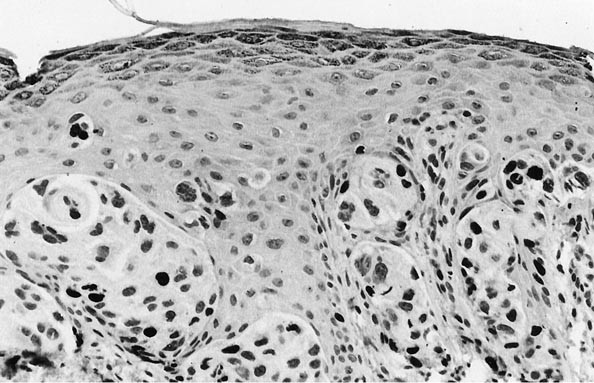

None of the common nevi showed more than 5% labeling for Ki-67, and all of them were completely nonreactive for p53 as well. The mean MIB-1 index was 0.5% in that group, with a range of 0 to 5% reactive cells (Tables 1 and 2). The majority of cases of CN (43 of 76 [57%]) failed to exhibit any nuclear staining. Likewise, SN demonstrated a very low Ki-67 index, ranging from 0 to 11% with a mean of 1.4% (Fig. 1); only one case of SN manifested more than 5% nuclear labeling. All SN likewise failed to label for p53. The results for LMMs and MCN were similar to those obtained in common nevi and SN; the average MIB-1 indices for those two forms of melanoma were 1.5% and 0.6%, respectively, and only 5% of LMMs and 4% of MCN were labeled for p53. The highest degree of both Ki-67 and p53 immunoreactivity was observed in NMMs. Seventy-eight percent of those tumors were p53 positive, and they had a mean proliferation index of 16.1% (Figs. 2 and 3). The only other group of melanocytic tumors with substantial p53 labeling (25%) was the SSMMs, in which an average Ki-67 staining index of 3.1% was obtained (Fig. 4). In aggregate, the proliferation indices of nodular melanoma and superficial spreading melanomas differed statistically from those of LMMs and melanomas arising in preexisting nevus (P <.05, χ2), but this obviously was due principally to the effect of data from the NMM group. Further corroboration of the latter point was gained from the observation that a statistically significant difference was also observed in the mean Ki-67 indices between SSM and NMM (P <.05, χ2). Conversely, p53 labeling was significantly and independently different for both the SSMM and NMM categories as compared with all other melanocytic lesions in the study (P =.035, χ2) (Fig. 5). Using a model with a 10% cutoff level for MIB-1 labeling and a 5% level for concurrent p53 immunoreactivity, 24 (75%) of the NMMs in this series could be correctly identified as in the vertical growth phase. In contrast, only five (8%) of the radial growth phase SSMMs showed similar findings in regard to the two markers being considered (Fig. 6). In the context of all melanomas in this study, the positive predictive value of the previously cited p53/Ki-67 threshold was found to be 83% for identification of the vertical growth phase.